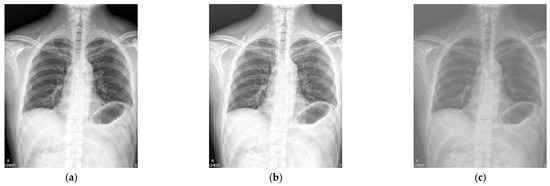

Figure 2 shows the enhancement images of eight approaches experimented on X-ray image 2. Figure 2a shows the original X-ray image 2; Figure 2b is the result obtained by McCann—the contrast is low; Figure 2c presents the image enhanced by RLBHE—it does not achieve the effect of image enhancement, the image is too dark, and we can hardly get effective information from it; Figure 2d shows the result achieved by RESIHE—the effect of enhancement is not obvious; the images obtained by TBCSSR and FuzzyII are shown in Figure 2e and Figure 2h, respectively. The contrast and the definition are low; Figure 2f and Figure 2g show the results enhanced by GDGIF and SMIPC, respectively. The two images appear to have noise amplification. The result enhanced by the proposed algorithm is shown in Figure 2i—it reveals more image details and suppresses the noise. Bone information can be clearly obtained, which is helpful for doctors to diagnose. Table 2 is the evaluation index values of various methods in Figure 2. Except for H, our method is the best for other indicators.

Figure 2.

Comparison on X-ray image 2. (a) Original image; (b) McCann; (c) RLBHE; (d) RESIHE; (e) TBCSSR; (f) GDGIF; (g) SMIPC; (h) FuzzyII; (i) Proposed method.

Table 2.

The metric data of eight methods on X-ray image 2.